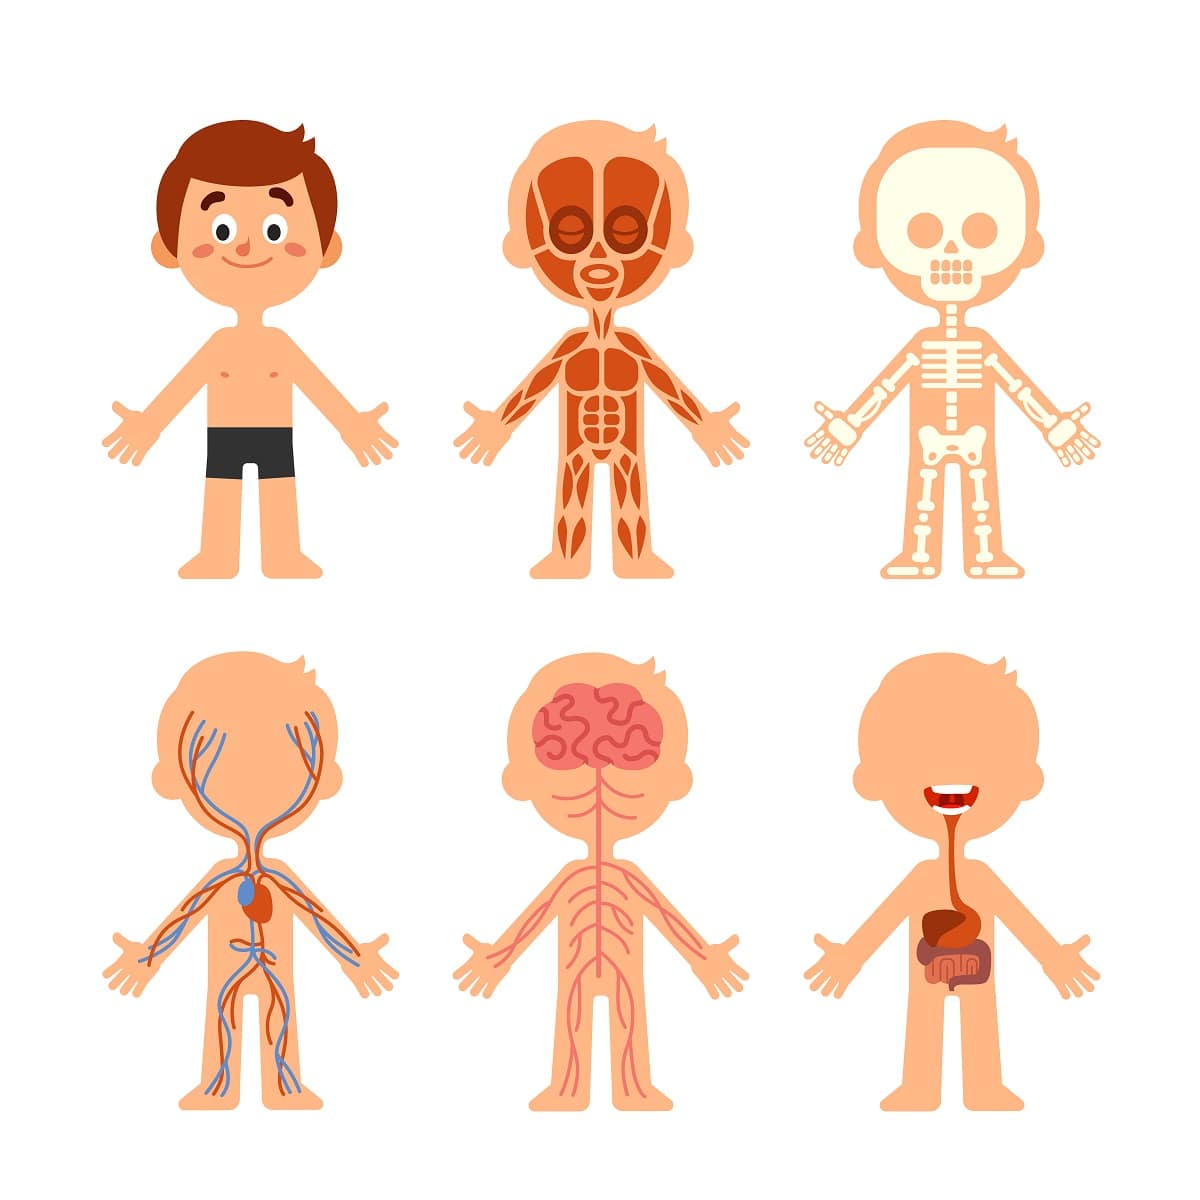

Esta rama de la anatomía subdivide al cuerpo en sistemas y los estudia describiendo su situación, forma, relación entre sus partes, constitución y estructura.

Establece divisiones por sistemas o de aparatos donde realiza un profundo estudio de cada uno de ellos. Por ejemplo, el sistema del esqueleto con sus músculos y ligamentos o vasos sanguíneos y linfáticos, etc.

Anatomía humana

Es la ciencia que estudia las estructuras macroscópicas del cuerpo humano. Estudia las estructuras del cuerpo humano por sistemas, como son, el sistema esquelético, el nervioso, el vascular, etc.